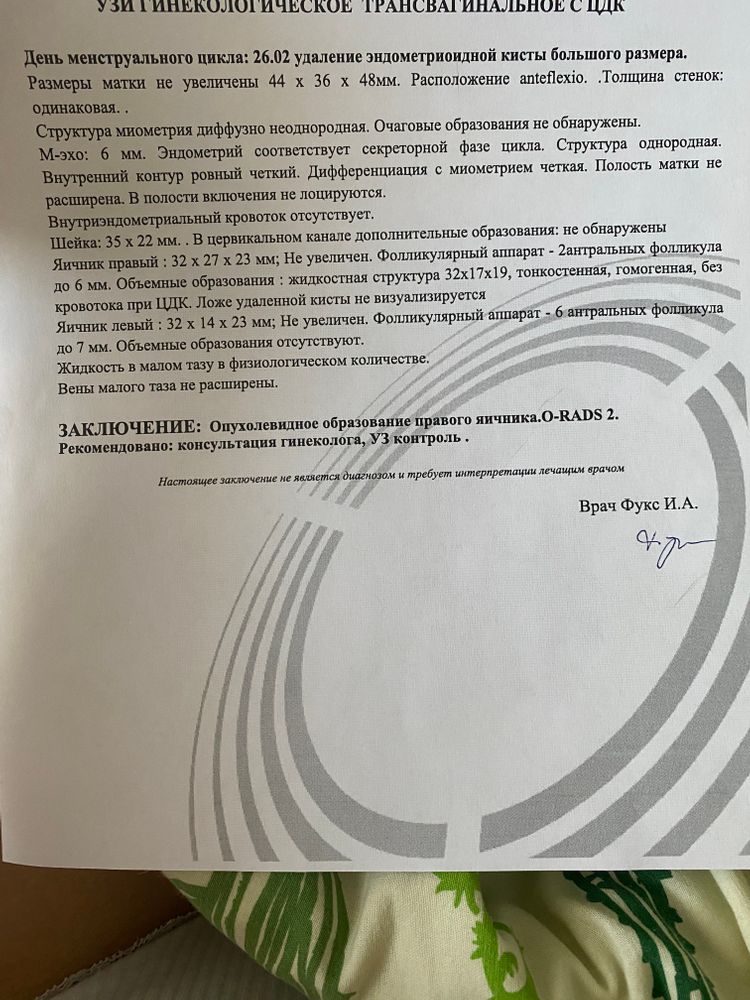

может кто-то сталкивался , принимаю визанну с 27февраля после лапароскопии по удалению эндометриойдной кисты яичника.

ходила на узи по поводу боли живота слева . Ничего не нашли .

На оперированном яичнике образование , врач сказал фолликулярная киста, частое явление на визанне .